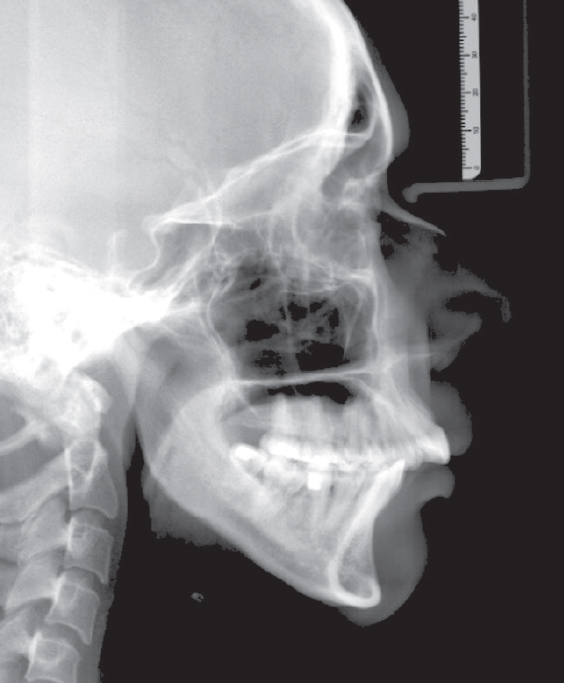

Computed tomography (CT) of the jaws, lateral cephalometric radiographs, TMJ CT, and functional diagnostic tests were performed (Figs. 4–6).

Fig. 6. Lateral cephalometric radiograph before treatment.

Рис. 6. Телерентгенограмма в боковой проекции до лечения.

After wearing occlusal splints for 6 months (Fig. 7), a follow-up lateral cephalogram was performed. When comparing the scans, anterior displacement of the mandible was detected (Fig. 8).

Fig. 8. Lateral cephalometric radiograph: before (a) and after (b) using the mouth guard.

Рис. 8. Телерентгенограмма в боковой проекции до (a) и после (b) использования каппы.